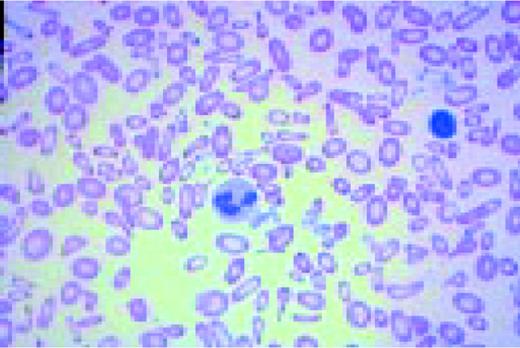

Slide L1

A normal peripheral blood lymphocyte and monocyte.FIG1